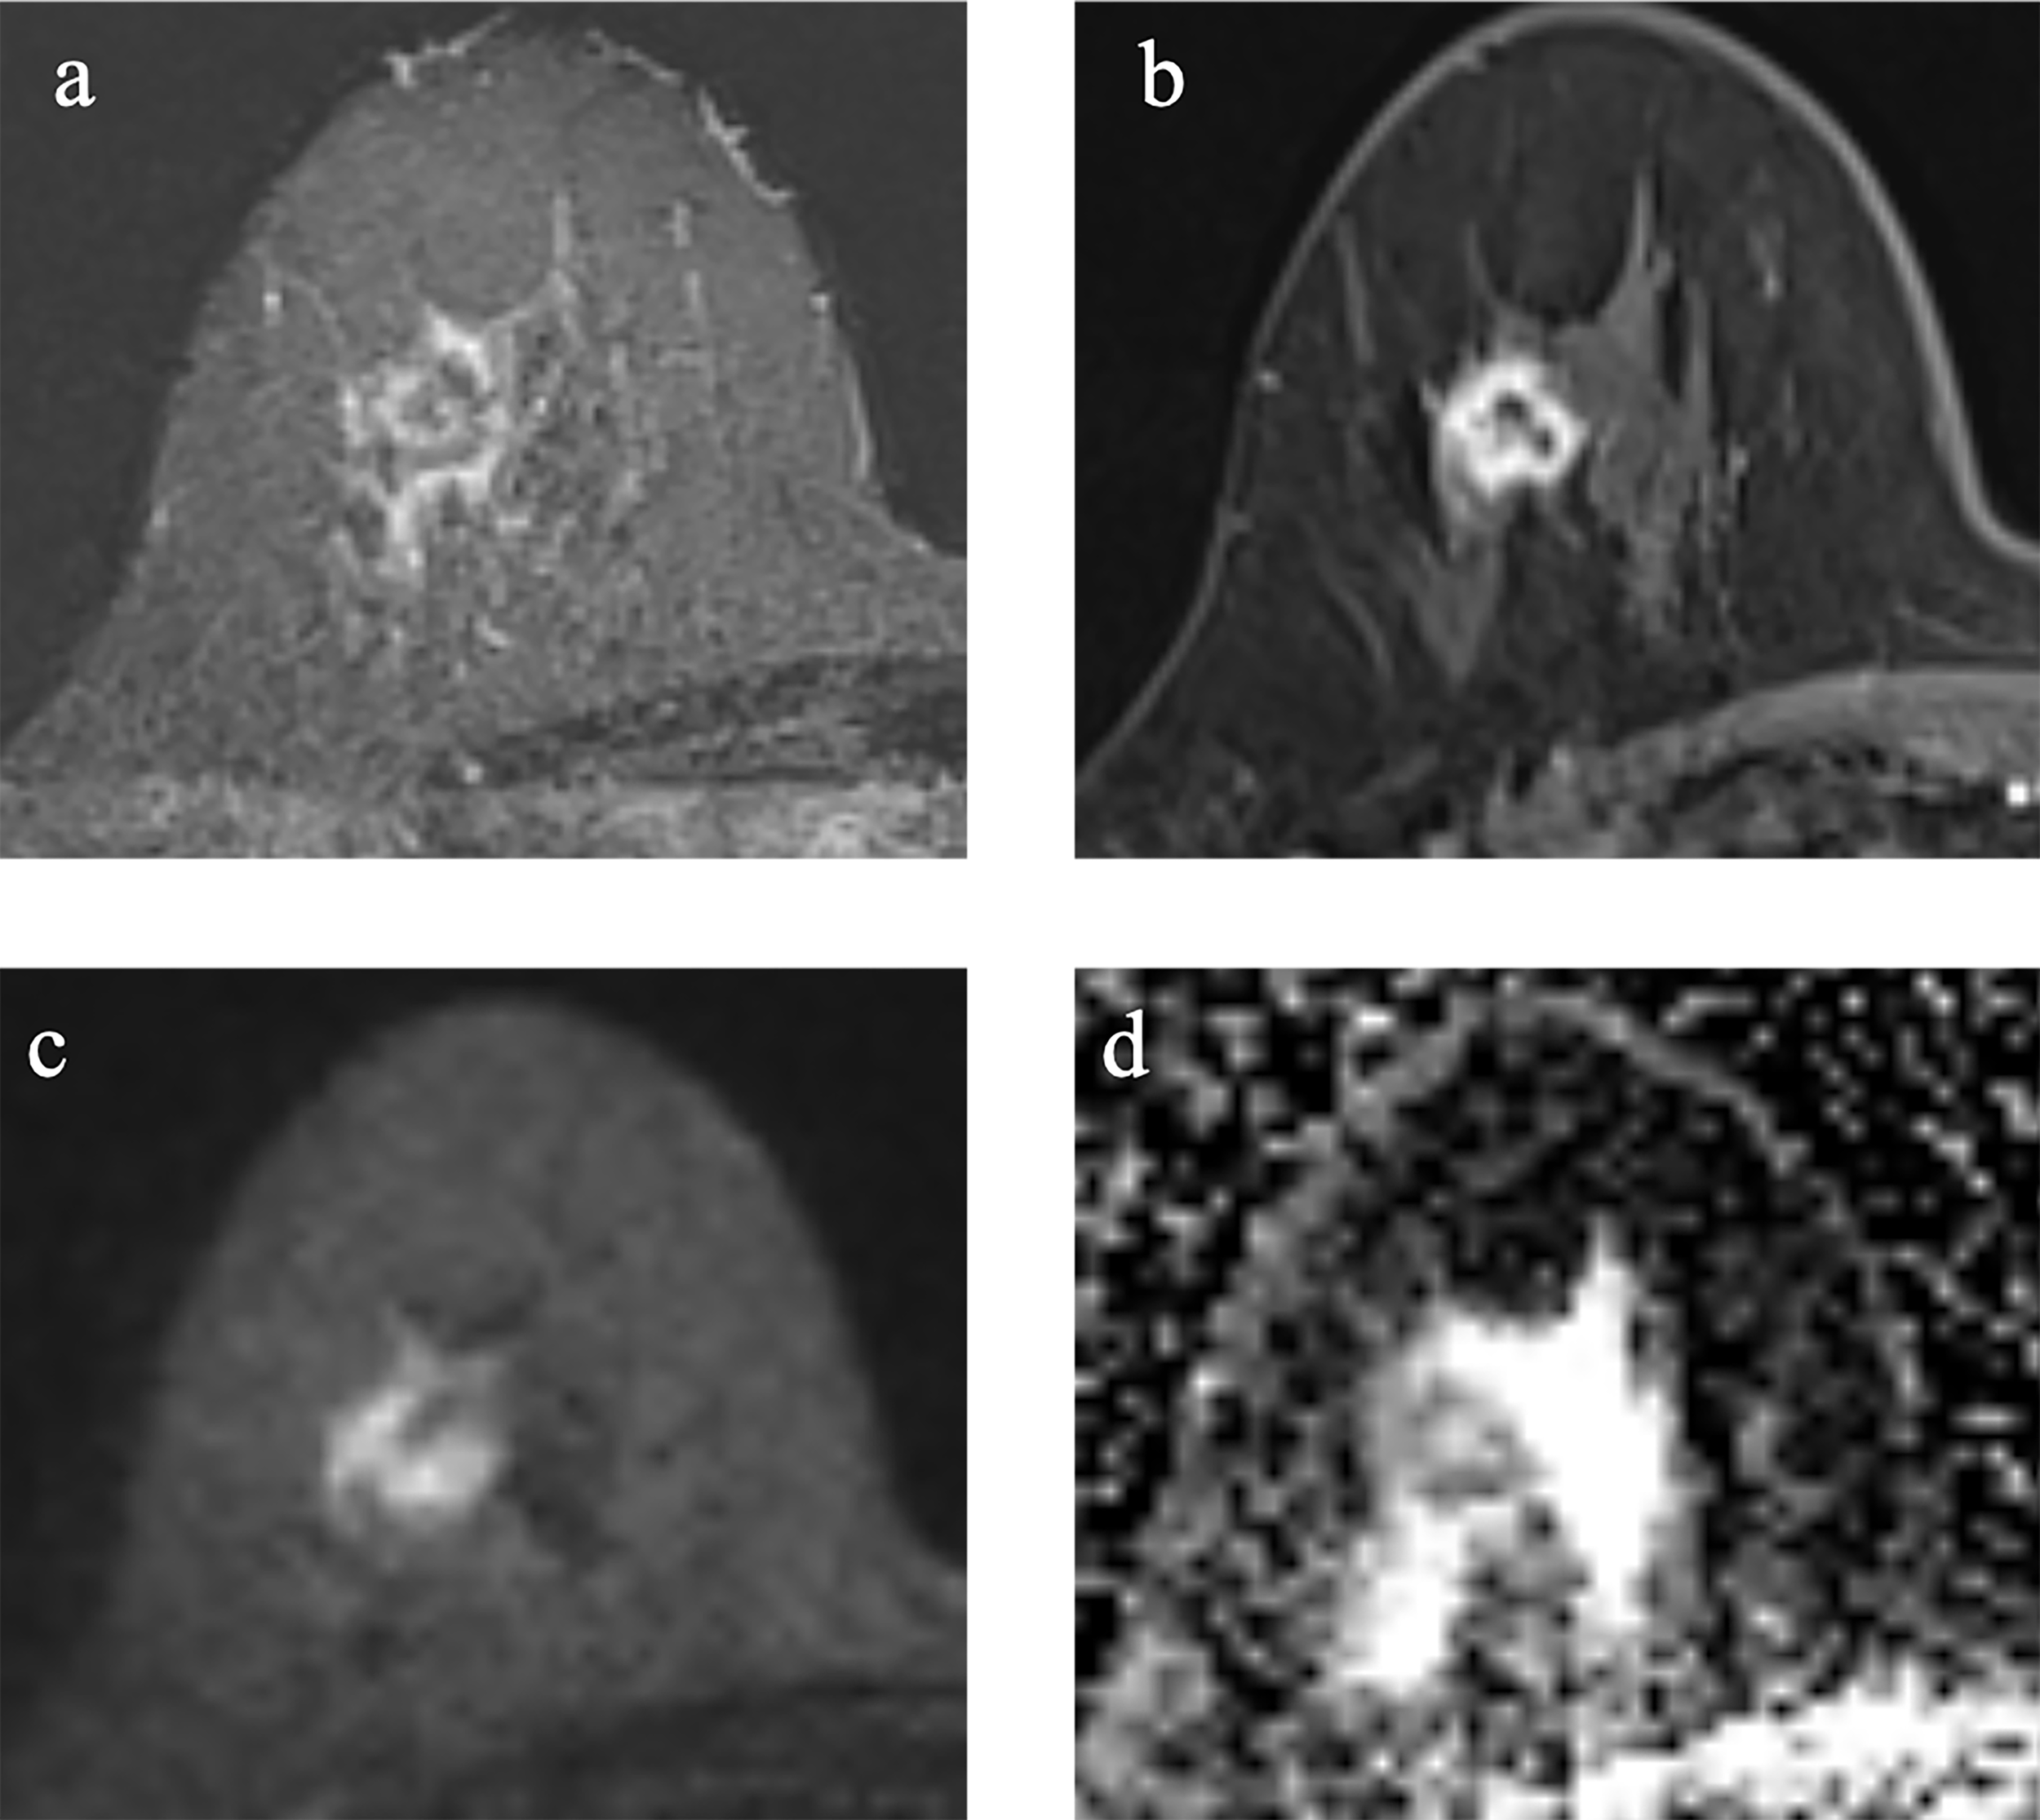

Of the 91 TNBC lesions, 66 lesions with TP53 mutations, and other 25 lesions without TP53 mutations. Cases of TNBC with and without TP53 mutations are shown in Figures 2, 3.

Figure 2

Example images of a 29-year-old woman with TNBC with TP53 mutation in the right breast (A-D). (A): T2-weighted-image. (B): the first phase of T1WI after contrast enhancement. (C): diffusion-weighted image of b1000. (D): apparent diffusion coefficient (ADC) map.

Figure 3

Example images of a 70-year-old woman with TNBC without TP53 mutation in the right breast. (A-D). (A): T2-weighted-image. (B): the first phase of T1WI after contrast enhancement. (C): diffusion-weighted image of b1000. (D): apparent diffusion coefficient (ADC) map.